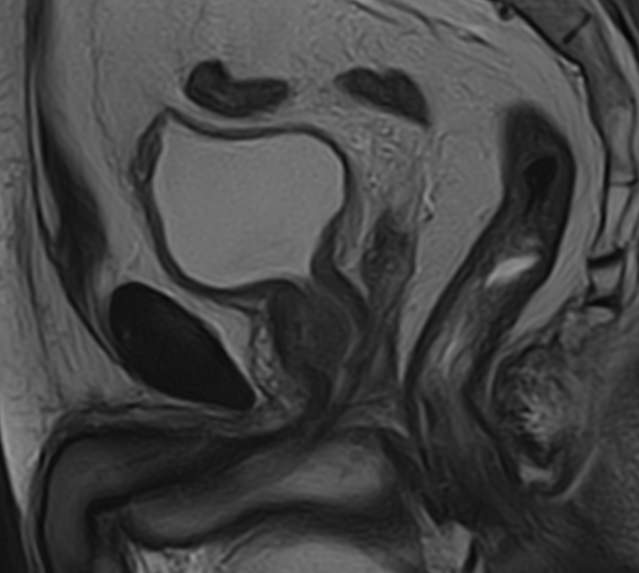

Магнитно-резонансная томография органов малого таза у мужчин подразумевает послойное сканирование анатомической зоны предстательной железы, мочевого пузыря с мочеточниками, прямой кишки и полости малого таза с окружающими мягкими тканями.

структуру предстательной железы, а также выявить происходящее в ней патологические процессы. К примеру, для таких заболеваний, как простатит, аденома простаты (доброкачественная гиперплазия) и рак простаты очень важна ранняя диагностика, что и позволяет МРТ. Для обследования простаты метод МРТ является уникальным по своей информативности.

Исследование проводится с наполненным мочевым пузырем (для оценки состояния самого мочевого пузыря), для этого ориентировочно за 1 час до процедуры нужно выпить 0,5 – 1 литр воды и не мочиться до окончания исследования.